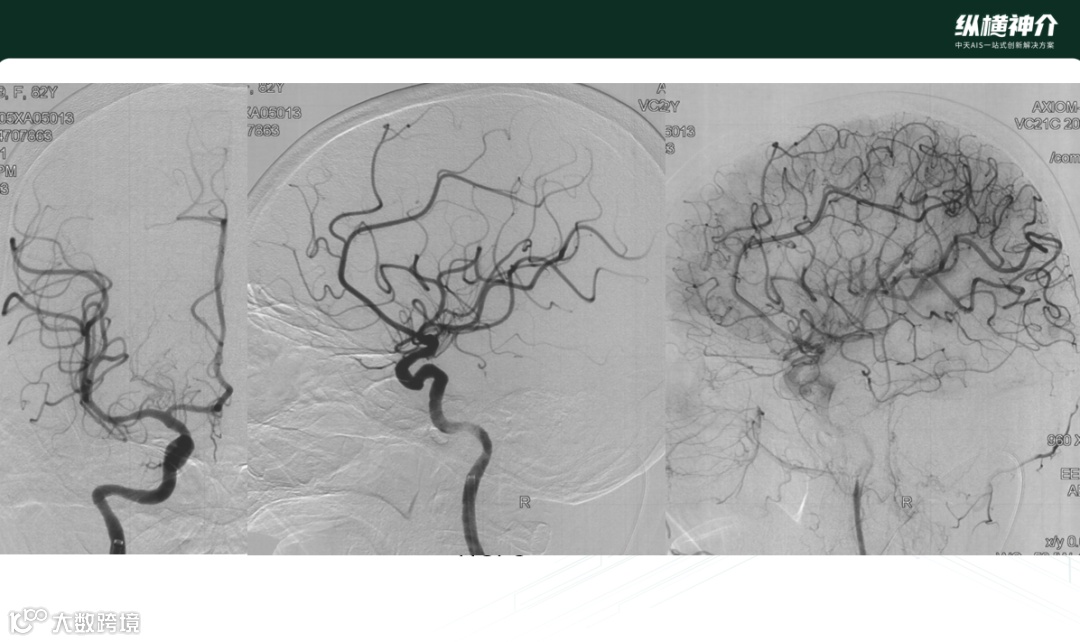

病例一

• 天弋®取栓支架显影性

• 一把即开通闭塞血管,达到mTICI3级血流再通